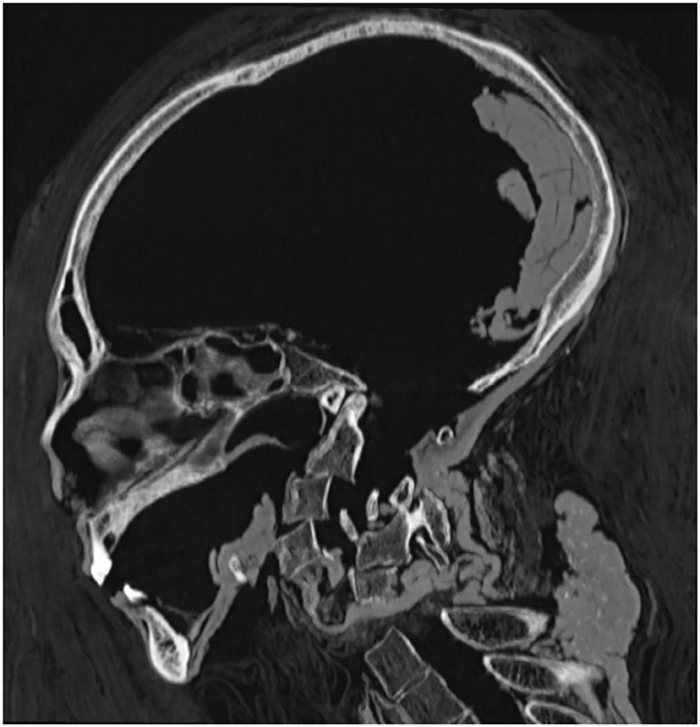

아래가 CT 스캔으로 촬영한 미라 머리의 단층 사진.

아멘호텝 1세의 미라를 3D 단층 촬영한 것은, 카이로 대학 의학부의 방사선과 의사인 사하르 살림 씨 등의 연구팀이다. 이들은 아멘호텝 1세의 미라를 CT 스캔으로 촬영하고, 단층 사진을 겹쳐서 비침습적으로 미라를 조사하는데 성공했다.